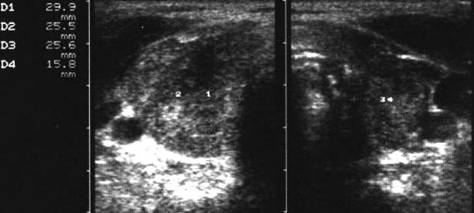

MetastaZE linfonodalE

Femeie de 65 ani. De 10 ani prima interventie de

tiroidectomie totala pentru neoplazie papilara infiltranta in tesutul muscular,

cu metastaze linfonodale. Terapie cu Iodi 131 in primii 5 ani.

Voluminoasa tumefactie laterocervicala dreapta (16 cc ) si paratraheala stanga

(3 cc), pozitiva la citoaspiratie pentru recidiva de neoplazie papilara.

Aceeasi de

65 ani. Nu se evidentiaza vascularizatie intratumorale

Femeie de 29 ani. Linfonodul in regiunea

laterocervicala dreapta ( 7x12x23mm, 1 cc) in neoplazie papilara a tiroidei. Structura

parenchimatoasa, neomogenea, cu margini

nete, cu absenta hilului.Examen citologic: metastaza de neoplazie papilara.

Lob drept,

proiectie trasversala si longitudinala

Aceeasi pacienta. Nodul de consistenta dura in lobul

drept spre istm.

Ecografia: nodul cu margini indistinte care deformeaza marginea anterioara a glandei,

parenchimatoasa, neomogena, hipoecogena. Prezenta de linfonodi laterocervicali.

Ctoaspiratie: carcinom papilar.